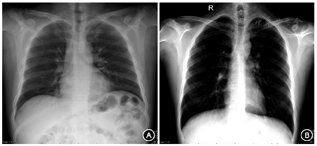

根据入选标准和排除标准初选病例56例,其中4例因间位结肠导致胃泡无法准确测量予以排除(图2A),共有52例病例的胃泡测量数据纳入统计,其中存在胃泡48例(92.3%)、4例未发现胃泡(7.7%),对照组13例中存在胃泡11例(84.6%),未见胃泡2例(15.3%)(图2B),胃泡存在率病例组与对照组间差异无统计学意义(P>0.05)。

注:A示存在间位结肠,影响胃泡判读;B示立位胸部平片中未见胃泡